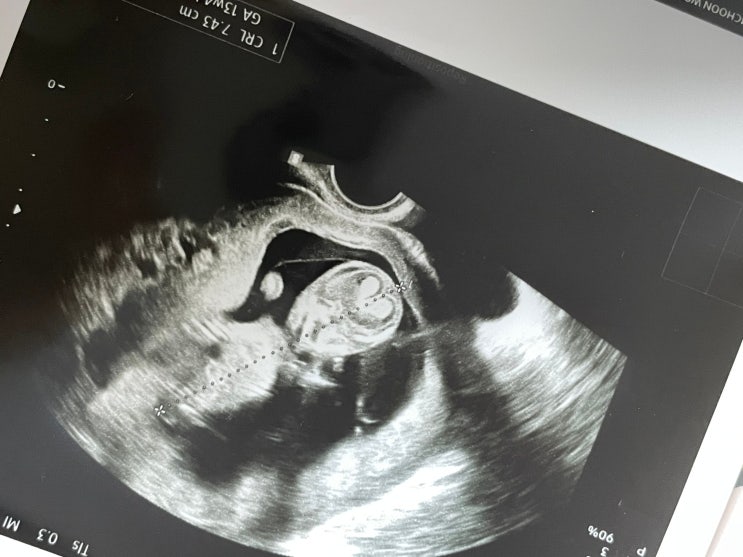

임신 12주차 | 기형아 검사, 융모막 검사 후기 (목투명대 3.9mm, 함춘여성병원)

안녕하세요, 임맹고입니다. ˙ᵕ˙ 오늘은 제가 임신기간 중 가장 힘들고 가장 많이 울었던 12주차 기형아 ...